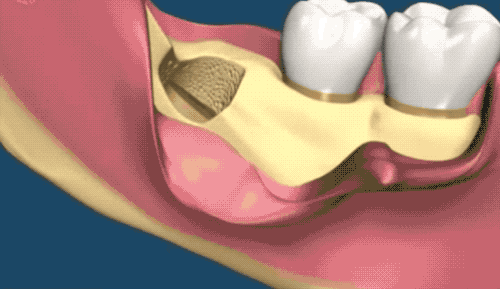

接著介紹下小編的牙齒類型,堪稱 hard 模式的橫阻生智齒。一般生長(zhǎng)情況也分兩種,一種是已經(jīng)出肉的,一種是還未出肉的,操作都差不多,我們就直接看下圖的介紹了。

露出牙槽骨后,先削除一部分骨頭,露出躺臥如睡美人的橫阻生智齒...如果是已經(jīng)出肉的智齒,就沒這一步了。

請(qǐng)出那令人聞聲喪膽的牙科渦輪機(jī),先分割智齒,撬出塊頭過(guò)大的牙冠來(lái)...再把牙根磨切兩半,依次撬出來(lái)。當(dāng)然這樣的操作并不都是必須的,牙醫(yī)會(huì)依據(jù)當(dāng)時(shí)的可操作性去處理,畢竟每個(gè)哈姆雷特的橫阻生智齒也都可能長(zhǎng)得不一樣。